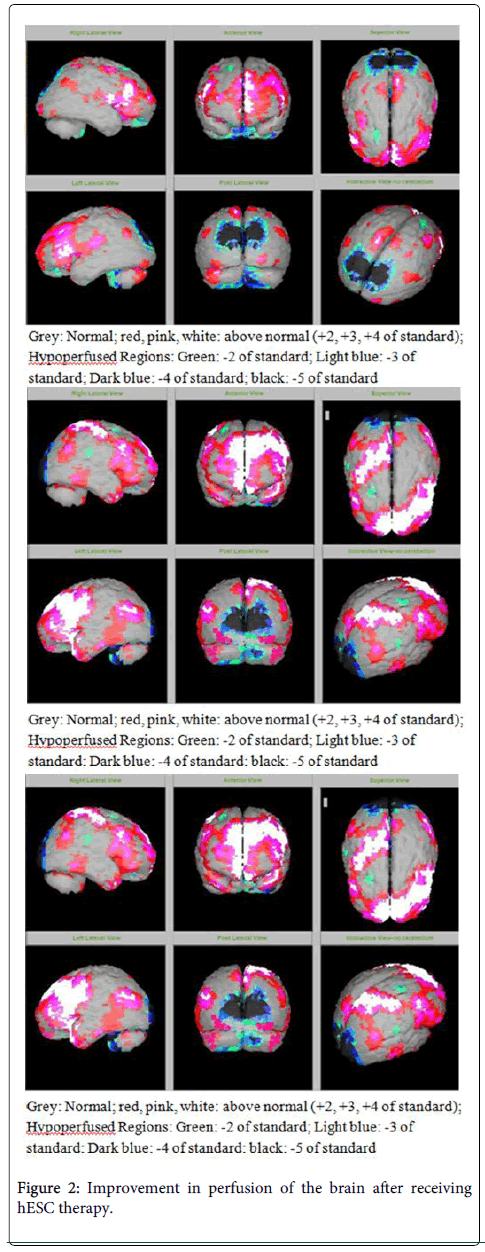

圖2:接受hESC治療后大腦灌注得到改善

在研究開(kāi)始和結束時(shí),23名患者接受了SPECT掃描。在枕葉或額葉或雙葉中觀(guān)察到灌注不足。23例接受SPECT掃描的患者中,5例患者表現為枕葉灌注不足,7例患者表現為額葉灌注不足,11例患者表現為枕葉和額葉灌注不足。

總體而言,治療結束時(shí),2名患者的灌注正常,18名患者(12名男性和6名女性患者)顯示灌注顯著(zhù)改善(>60%),3名患者顯示灌注中度改善(30-60%)。大多數在接受hESC治療前額葉和枕葉嚴重低灌注的患者在接受 hESC 治療后情況有所改善。23名可獲得SPECT掃描報告的患者的GMFCS評分在hESC治療后有所改善(表2)。

眾所周知,神經(jīng)干細胞可以通過(guò)重新填充受損區域并防止細胞進(jìn)一步退化來(lái)恢復正常視力。hESC通過(guò)增殖成相似的細胞類(lèi)型來(lái)啟動(dòng)受損細胞的再生。在本研究中觀(guān)察到灌注改善,這反映在SPECT掃描中。詹森等人研究顯示,一名5歲腦癱患者在接受臍帶血干細胞治療2個(gè)月后視力有所改善。